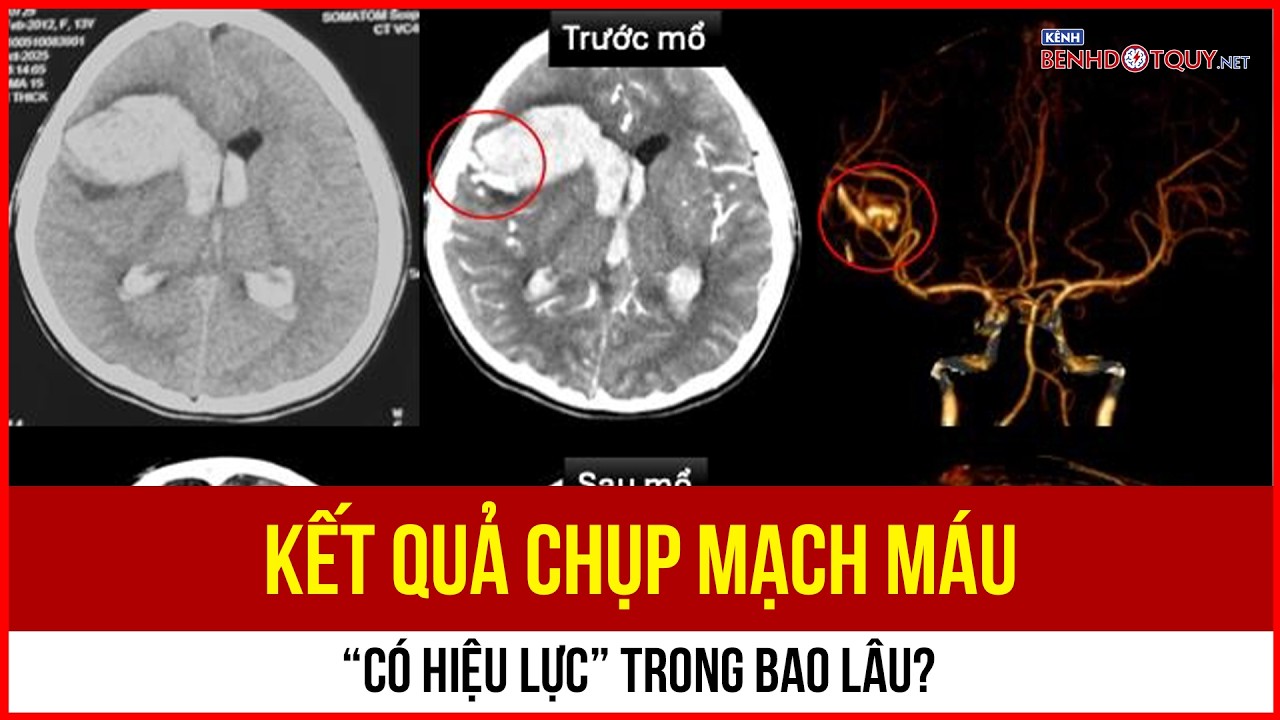

Kết quả chụp mạch máu “có hiệu lực” trong bao lâu?

Kết quả chụp mạch máu là căn cứ quan trọng giúp bác sĩ chẩn đoán và theo dõi bệnh lý tim mạch, đột quỵ. Tuy nhiên, nhiều người vẫn băn khoăn liệu những hình ảnh này có thể sử dụng trong bao lâu trước khi cần chụp lại. Thực tế, “giá trị” của kết quả không phải lúc nào cũng cố định, mà phụ thuộc vào diễn tiến bệnh và tình trạng sức khỏe của từng người.

Kết quả chụp mạch máu “có hiệu lực” trong bao lâu?

Kết quả chụp mạch máu là căn cứ quan trọng giúp bác sĩ chẩn đoán và theo dõi bệnh lý tim mạch, đột quỵ. Tuy nhiên, nhiều người vẫn băn khoăn liệu những hình ảnh này có thể sử dụng trong bao lâu trước khi cần chụp lại. Thực tế, “giá trị” của kết quả không phải lúc nào cũng cố định, mà phụ thuộc vào diễn tiến bệnh và tình trạng sức khỏe của từng người.